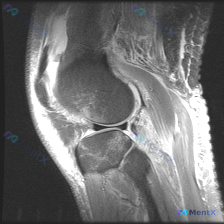

看到一个很有代表性的读片病例,怀疑半月板异常但单张T1加权MRI没有发现明确问题,整理了分析思路和大家分享。 病例核心信息 问题:临床怀疑半月板异常,提供单张膝关节矢状位T1加权MRI,需要做影像观察和分析 影像系统性观察结果 1. 骨性结构:股骨远端、胫骨近端、髌骨轮廓规整,骨髓信号正常,未见骨质...